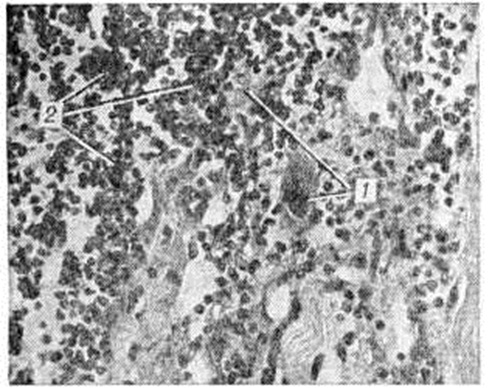

Миозит при туберкулёзе протекает по типу интерстициального с туберкулёзными гранулемами или формируется холодный абсцесс (смотри полный свод знаний Натёчник), в котором определяется очаг коагуляционного некроза и грануляционная туберкулёзная ткань. Для сифилитического Миозит характерен диффузный склеротический процесс, реже в толще мышц встречаются гуммы. Миозит при ревматизме в зависимости от активности патологический процесса может протекать с преобладанием экссудативных, деструктивных или пролиферативных изменений и наличием типичных ревматических гранулем. При полифибромиозите гистологически выявляются серозный выпот, лимфоидно-гистиоцитарные инфильтраты, очаговые дистрофические и некротические изменения в мышечных волокнах с последующим склерозом эндо и перимизия. При полимиозите макроскопически мышцы отёчные, бледные, с очагами некрозов и кровоизлияний; при хроническом течении заболевания они уплотнены вследствие разрастания фиброзной ткани. Гистологически при остром полимиозите наблюдается паренхиматозно-интерстициальное воспаление с выраженными дистрофическими (зернистая, гидропическая, жировая) и некротическими (миолиз, коагуляционный некроз) изменениями мышечных волокон и преимущественно периваскулярной крупноочаговой лимфоидно-макрофагальной инфильтрацией (рисунок 1). Выявляются признаки макрофагальной резорбции и внутриклеточной регенерации с пролиферацией субсарколеммальных ядер. При хронический полимиозите (рисунок 2) отмечается сочетание процессов атрофии, гипертрофии и деструкции мышечных волокон, склероза и липоматоза эндо и перимизия. Часть мышечных волокон подвергается обызвествлению. Вовлечение в воспалительный процесс периневрия ведёт к деструкции миелиновых оболочек и осевых цилиндров нервных стволов с развитием нейромиозита.

Рис. 1.

Микропрепарат мышечной ткани при остром полимиозите (продольный срез): дистрофия и некроз мышечных волокон (1), лимфоидно-макрофагальная инфильтрация (2); × 280.

Рис. 2.

Микропрепарат мышечной ткани при хроническом полимиозите (поперечный срез): разнокалиберность мышечных волокон, склероз эндо и перимизия (указано стрелками); × 280.